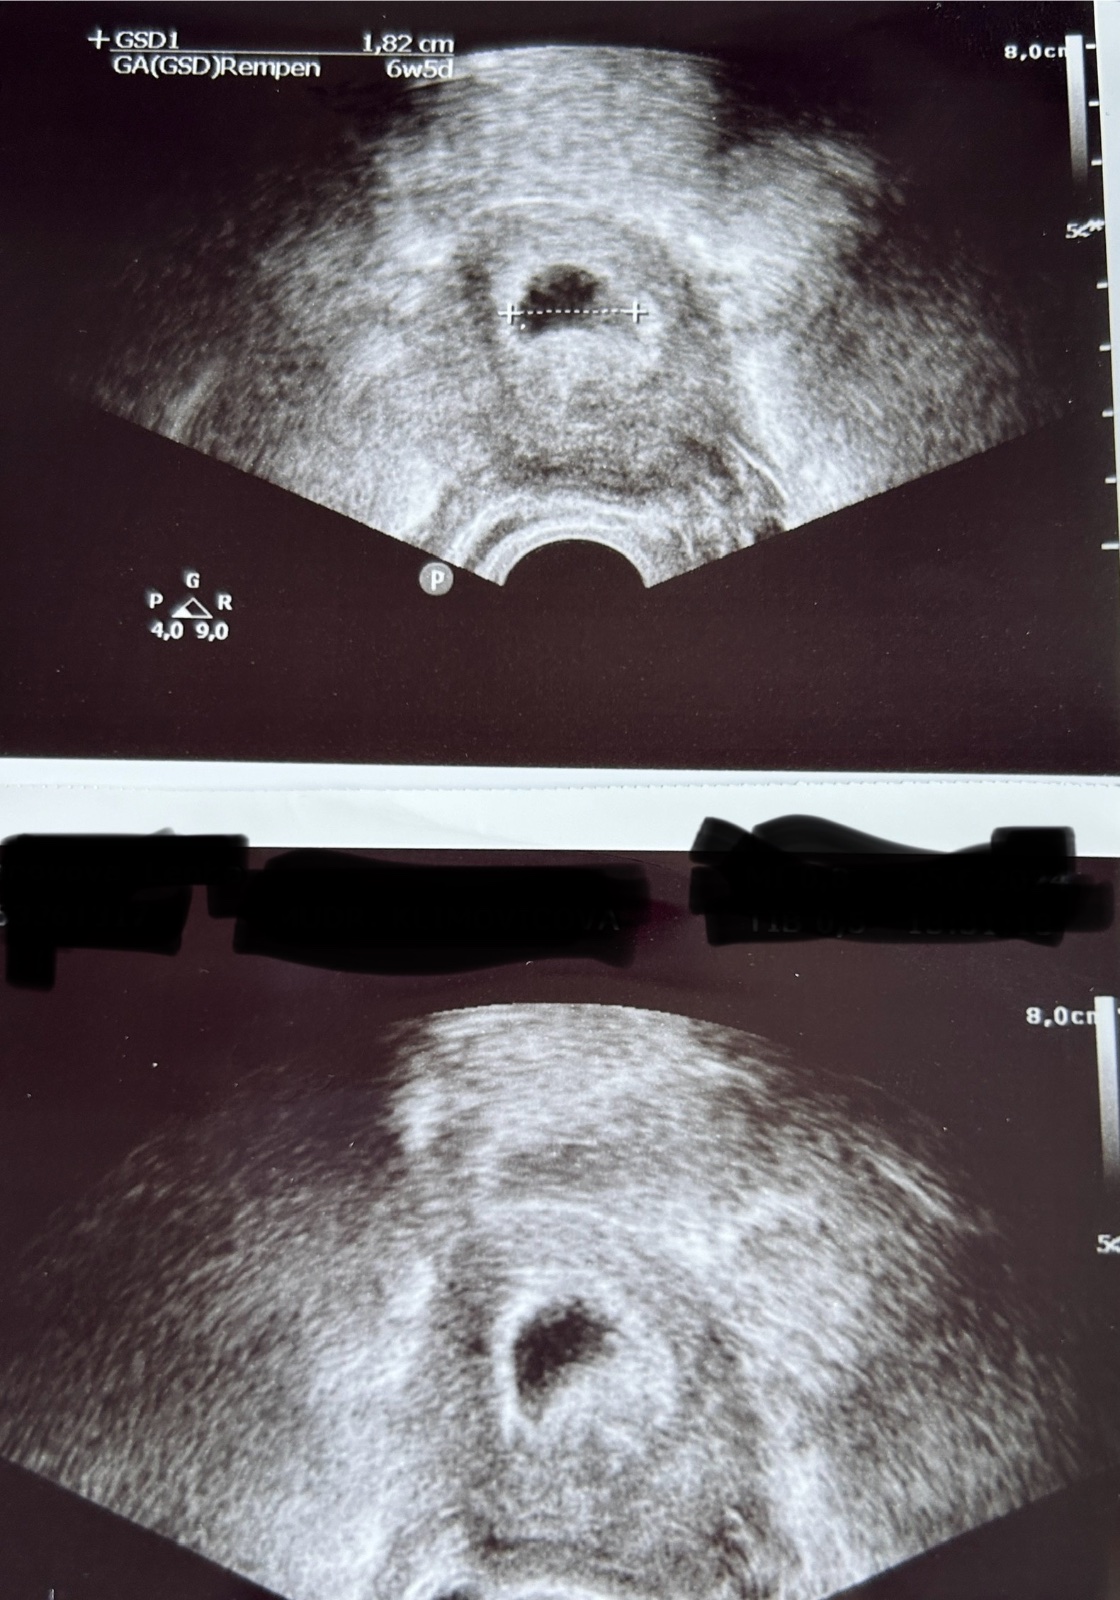

Gestační váček v 6. týdnu těhotenství. Co dál?

@sabinazidkova20 Uplně nevím ovulaci, kdy byla. Ale podle ultrazvuku jsem 6. týden. Tak já nevím.

Jen neviděla plod, ale říkala, že žloutkový váček vidí, ale potom mi řekla, že to může být i anembryomola. Tak jsem z toho smutná.

Musela jsem jít na prohlídku už teď, mám za sebou už 2 potraty. Tak proto jsem šla už teď. No uvidíme. Ale váček je v pořádku, vypadá tak jak má vypadat? Je už dost veliký 18mm, ale plod neviděla.

A vypadá ten váček v pořádku? Má takhle vypadat?…